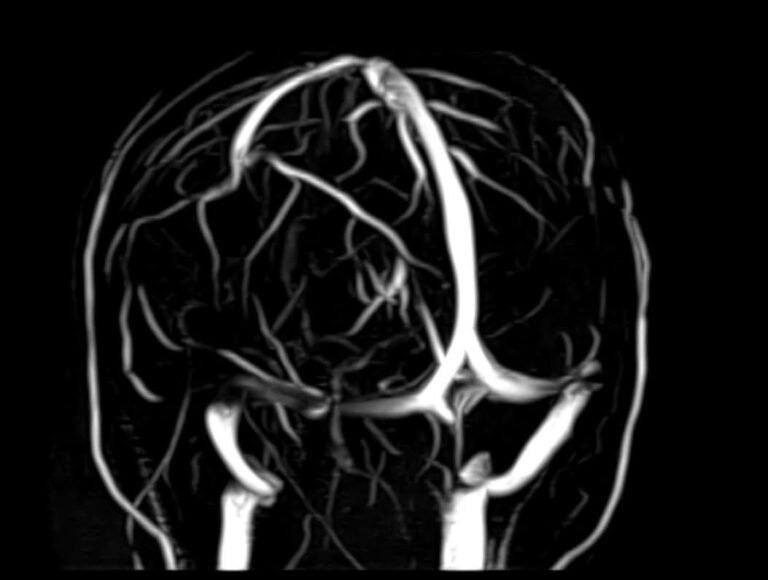

МРТ головного мозга является высокоинформативным методом исследования центральной нервной системы, который дает возможность оценить состояние всех структур головного мозга и поставить правильный диагноз. Стандартную МРТ головного мозга дополняет МР-венография, которая позволяет получить детальную картину строения и функционального состояния венозной системы мозга.

В клинике «Доступная медицина» проводится МРТ головного мозга и МР-венография головного мозга на современном аппарате TOSHIBA VANTAGE TITAN 1,5 Тесла, который обладает высокой чувствительностью и соответствует всем мировым стандартам качества диагностики. Напряженность магнитного поля 1,5 Тесла обеспечивает высокую четкость изображения и позволяет выявлять заболевания на ранних стадиях развития. Процедура МРТ безопасна, так как томограф не испускает рентгеновского излучения, полностью безболезненна и имеет доступную стоимость.

• участки сужения, извитость, образование петель и перегибов сосудов;

• нарушения оттока крови за счет тромбообразования в венозном русле;

• ангиомы, сосудистые мальформации.